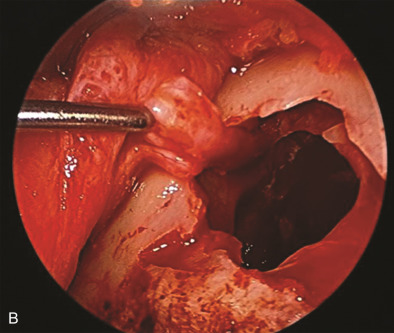

The maxillary division carries sensory information from the lower eyelid, cheek, upper lip, upper teeth, and associated mucosa. The zygomatic nerve gives its terminal branch as the zygomaticofacial nerve that supplies sensation to the lateral cheek and portions of the forehead. The terminal branch of the maxillary nerve exits the facial skeleton as the infraorbital nerve. This nerve is encountered regularly in midface injuries as well as orbital floor fractures ( Fig. 3.16.3 ). The mandibular division is the largest branch of the trigeminal nerve. Before the mandibular nerve enters the medial mandible at the lingula, it will bifurcate and the lingual branch will course within the soft tissue of the floor of the mouth, where it will be in intimate association with the submandibular duct. The terminal branch of the mandibular nerve will enter the medial mandible within the inferior alveolar canal and exit at the mental foramen to give sensation to the mandibular dentition, mucosa, and lower lip. Both of these nerves can be encountered in mandibular fractures as well as soft tissue injuries to the submandibular region ( Fig. 3.16.4 ).